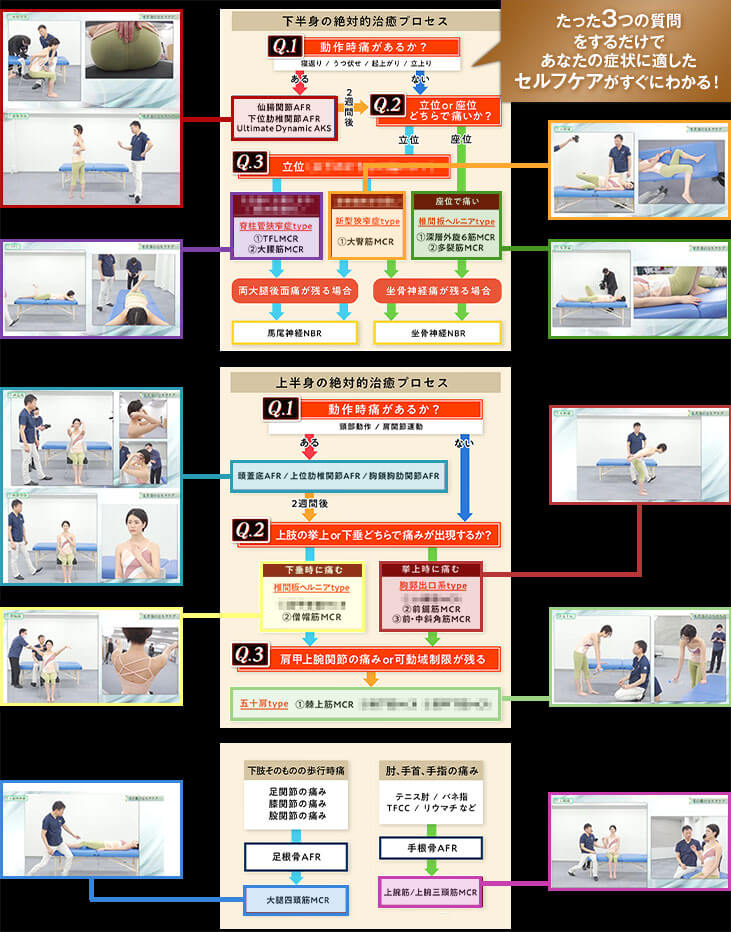

これが、AKS療法®の絶対的治癒プロセスです。この図は患者さんが来た時の問診時に使えるフローチャートになっており、あなたは上半身、下半身それぞれに対応する3つの質問「Final 3 Qestion」を患者さんに聞き、絶対的治癒プロセスに則ってチャートを進むだけで、原因が明確になり、アプローチする手技が明確になるのです。

- ①フローチャートに沿って誰でも出来る3つの質問をする

⇒医師も分からない真の症状の原因が浮き彫りに! - ②チャートから導き出された手技をやるだけ

この絶対的治癒プロセスを使えば、たとえあなたが解剖学をまったく知らない素人だとしても、患者さんの痛みの真の原因が分かるようになるので、原因が分からずに全身を揉んでみたり、治療に悩んだり不安になることがなくなるのです。

つまり、この絶対的治癒プロセスはゴッドハンドと同じ診立てや問診、治療計画を立てるためのカンニングペーパーのようなものであり、手技の使い方をナビゲートしてくれるものです。

この、たった3つの質問で症状の根本原因を明らかにし、患者さんの未来予測までできるようになる絶対的治癒プロセスと手術宣告された重症患者さんでも回復に導く手技の両方が揃っている最強の治療法が「AKS療法®-Final-」であり、“素人でも重症患者さんを回復に導ける”と自信を持っておススメできるのです。

殺到するほど効果が高い - たった3つの質問をするだけで、

根本原因が明確になる - 手術宣告された “重症患者ほど”